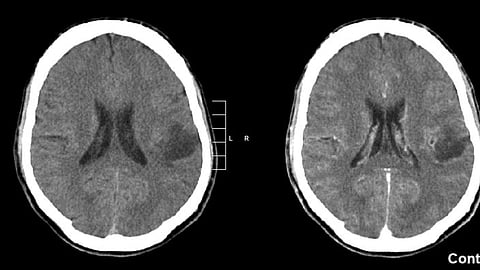

An important new clue for preventing and treating brain tumors known as gliomas has been identified in research led by the Lunenfeld-Tannenbaum Research Institute (LTRI) at Mount Sinai Hospital in Toronto and Mayo Clinic Comprehensive Cancer Center and Mayo Clinic Center for Individualized Medicine. The study, published in the journal Science, provides a rare window into the biological changes behind glioma development.

The study offers new knowledge that may help clinicians determine, pre-surgery, whether a patient has a glioma.